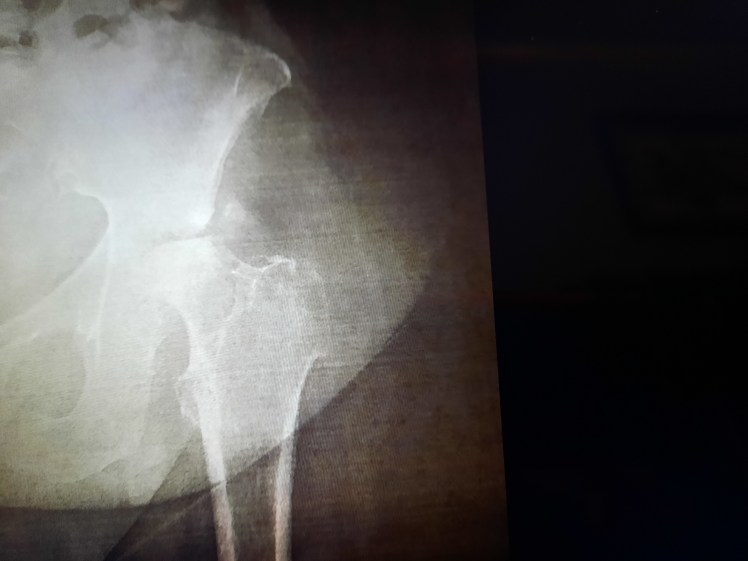

The head of the femur fits into the socket provided by the pelvis. I had an x-ray of my hip from February and the hip joint was fine. The MRI of the hip that was last taken revealed an eroded head of my left femur. The top of the femur should look like a ball. Notice the top of the hip joint and you will see the head is eroded.

The Orthopedic Surgery Specialist saw the erosion of the head of the femur and told me, usually he could wait a month to do surgeries for this. But in my case, he felt he needed to get it done sooner. About two weeks later I was in surgery for a hip replacement (hip arthroplasty).